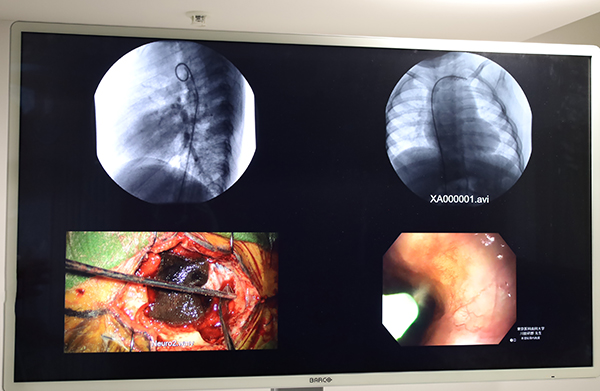

最後に,サージカル&モダリティ事業部長の今井勝正氏が登壇し,非圧縮IPビデオソリューション「Nexxis」による映像配信/画像統合ソリューションや,新製品の4K UHD解像度55インチ外科用ディスプレイ「MDAC-8355」を紹介した。MDAC-8355は,ディスプレイ自体に同社独自の画像合成機能を搭載し,Nexxisや画面分配器を使用することなく最大16レイアウトのマルチモダリティ画像を表示できる。また,モダリティ(画像)ごとに解像度や色温度,表示モードの設定が可能で,輝度安定性やDICOMキャリブレーションが保証されている。今井氏は,これらの性能や特徴を解説し,さらにディスプレイ単体のため価格面で導入ハードルが低いというメリットを挙げた。一方,Nexxisではアンギオ/X線TV手術室向けソリューション「Nexxis IVR Solution」や,操作室のワークフローを改善し,低コストかつ簡便に院内映像配信ソリューションを構築する「Nexxis WorkSpot」,ITEM2022で初展示されたライブシステム「Nexxis Live」が紹介された。Nexxis Liveは,リアルタイムに手術室の映像や音声を双方向で外部配信でき,標準ライセンスでは6名が外部からコラボレーションモードで同時参加し,会話やチャット,アノテーションでコラボレーションが可能である。今井氏は,これらのラインアップにより,手術室や検査室,操作室への対応や院内外への配信が可能となり,システムがコンプリートされたと述べた。

プレゼンテーション後にショールームで行われた製品デモンストレーションでは,新製品のMDAC-8355をはじめとする各装置のほか,ITEM2023で参考展示予定の超音波診断装置用ディスプレイ「MDAC-2323 Dual-layer LCD display」などが紹介された。

新製品の4K UHD解像度55インチ外科用ディスプレイ「MDAC-8355」。画面ごとに解像度などが設定可能。